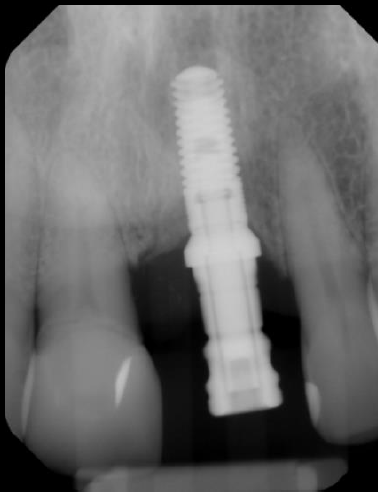

Immediate implant placement on #19 with custom healing abutment